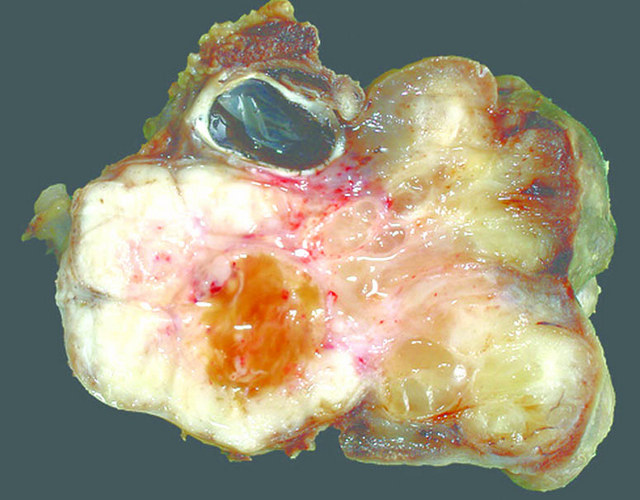

Gross description

- Poorly circumscribed mass, white, soft or firm, infiltrative

- Botryoid variant: resembles cluster of grapes or allergic nasal polyp, fleshy nodular polypoid projections of variable size into lumen

Gross images

AFIP images - botryoid variant